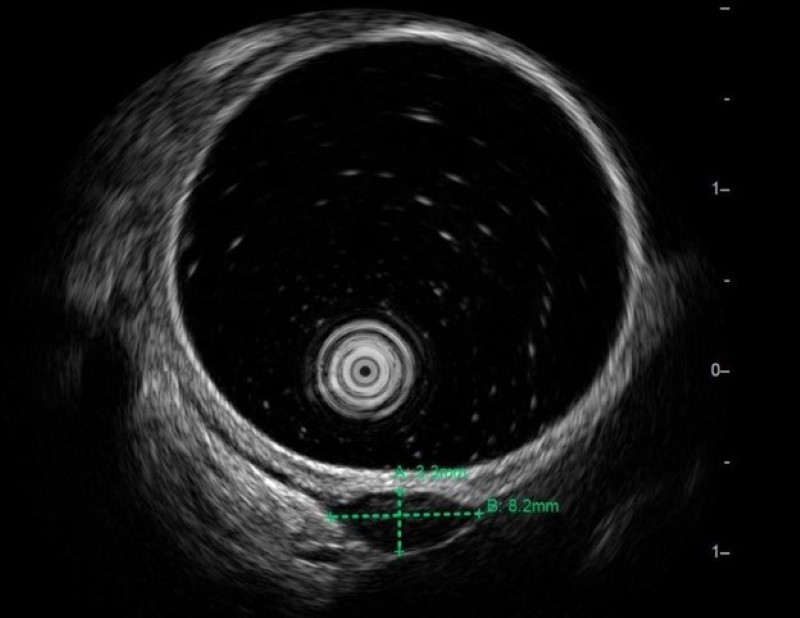

Kết quả cho thấy khối u kích thước khoảng 8,2 x 2,2mm, xuất phát từ lớp cơ trơn, ranh giới rõ, cấu trúc giảm âm đồng nhất, không vôi hóa, không chảy máu. Các đặc điểm này gợi ý nhiều đến u cơ trơn lành tính, nhưng vẫn chưa loại trừ GIST, một tổn thương khác nguy cơ cao hơn.

Khối u được phát hiện trên hình ảnh siêu âm nội soi. Ảnh BV